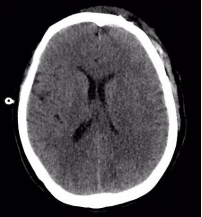

附女士,今年50岁,因车祸头部受伤,意识障碍4小时急诊入院。入院时,患者呈昏迷状,左侧瞳孔散大,头部、腕部、腹部等受伤10余处。急诊CT提示硬膜外血肿,中线移位明显,脑实质明显受压内移,左侧侧脑室受压变窄,病情凶险,手术指征明确。

(术后血肿清除彻底)

术后第一天,患者意识恢复清醒,复查头部CT提示颅内血肿清除彻底。全腹CT、双腕关节CT显示:肠管管壁明显水肿增厚,邻近肠系膜肿胀,肠间隙模糊,盆腔少量积液,腹腔内未见游离积气,提示肠管或肠系膜损伤;右侧月骨脱位,左侧桡骨远端骨折。